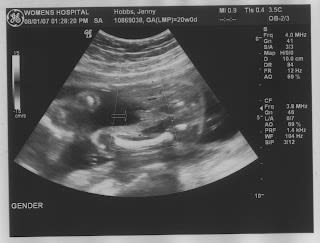

I had my ultrasound today and the technician wasn't sure of the gender of our baby but she decided that it's probably a boy... here are some pictures of our cute little Mario.

Little...boy part